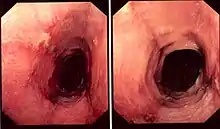

| Pathology image of lymphocytic esophagitis (H&E stain). The image demonstrates common findings in the condition: dense peripapillary lymphocytic infiltrate with spongiosis (arrow), and absence of neutrophils and eosinophils. | |